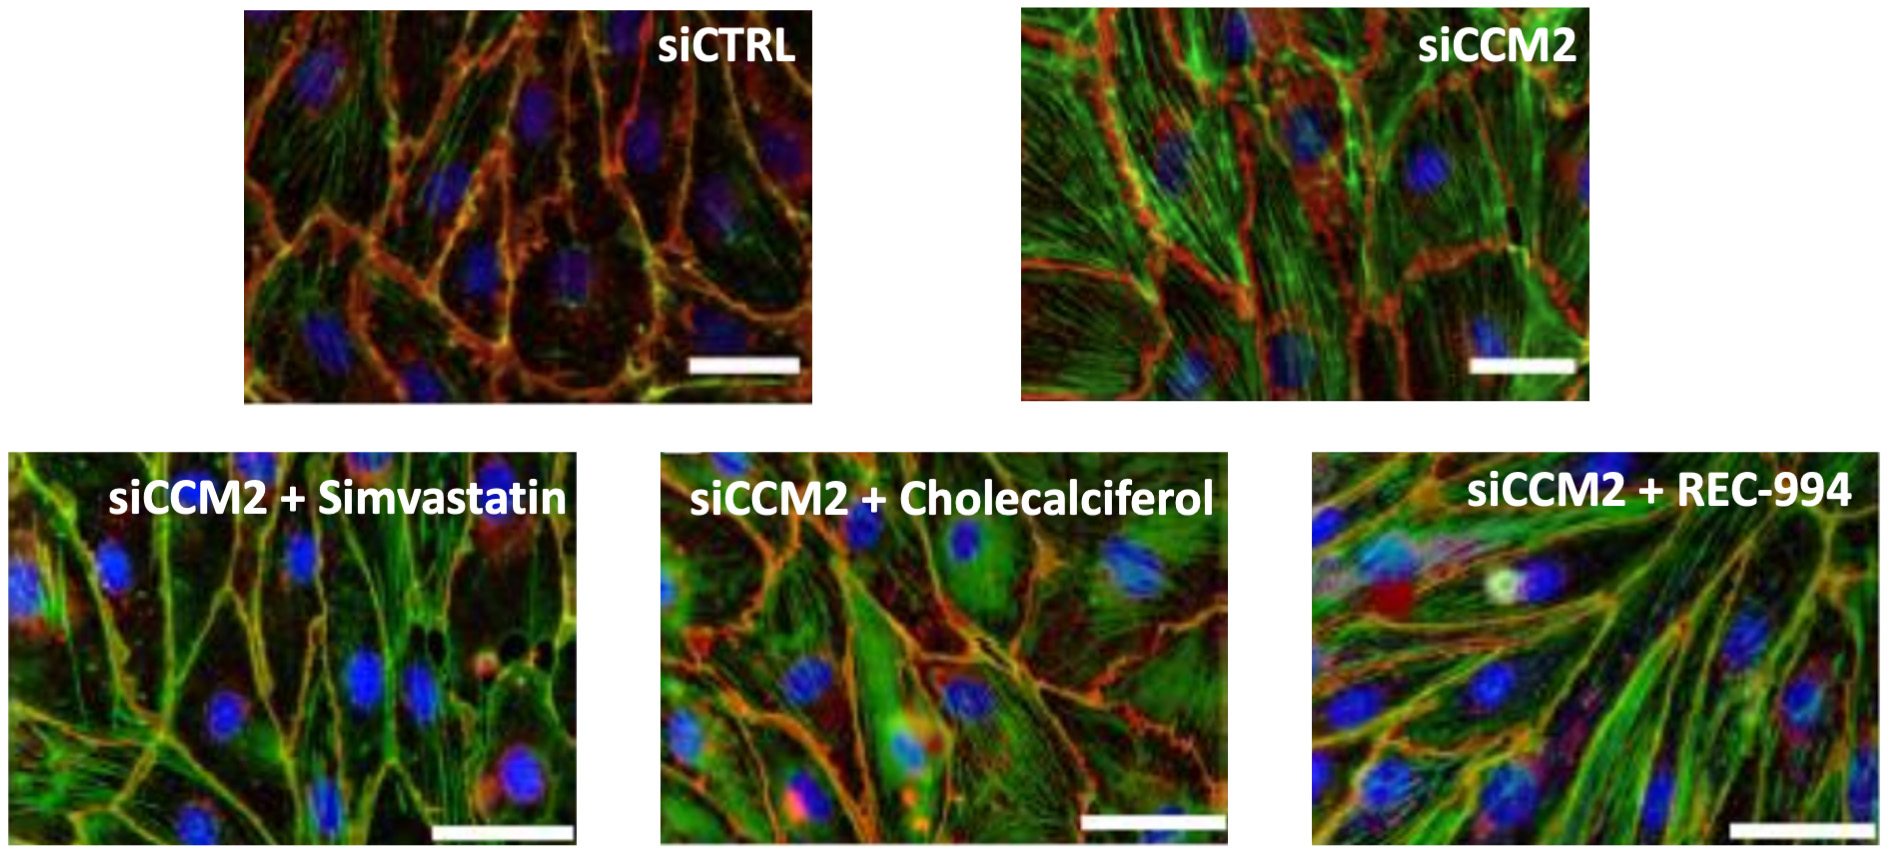

•Five phase 2 clinical-stage programs with multiple upcoming data readouts expected, including REC-994 in cerebral cavernous malformation (CCM) in Q3 2024, REC-2282 in neurofibromatosis type 2 (NF2) in Q4 2024, REC-4881 in familial adenomatous polyposis (FAP) in H1 2025, and REC-4881 in AXIN1 or APC mutant solid tumors in H1 2025

| | What’s more, the signs of AI-enabled point-solutions are already plentiful across our industry: •Protein folding •Scaled protein-ligand interaction prediction •Generative AI for chemistry for tractable targets •The FDA is already discussing the use of LLMs for program review •Major pharma companies are drafting regulatory filings like INDs by LLMs These facts lay out a clear future where efficiencies and improvements across the many current AI-enabled point-solutions will begin to combine into integrated ‘tech-stacks’ and workflows that will result in compounding improvements in our ability to drug historically undruggable targets, understand the underlying networks of biology with increasing fidelity, fast-follow newly validated biology, characterize disease in increasingly robust ways and ultimately deliver more, better medicines to patients to alleviate suffering at scale. The question is no longer whether this sort of future is before us, but when and who will lead it. Looking Back at 2023 and Before Reflecting back on late 2013 when Recursion was founded and how far we have come, it is simultaneously incredible and unsurprising to see where we are today. Recursion was then a Utah-based startup founded by two graduate students and a professor. Our first office was a conference room in the nearby University Research Park and our first laboratory was a converted storage room. Today, Recursion is a multinational, clinical-stage company leading the transition of BioTech into TechBio. We have over 500 employees, five clinical stage programs, one of the world’s largest biological and chemical datasets and two of the largest discovery collaborations in the industry with Roche/Genentech and Bayer. And in 2023, the opportunity ahead feels so much greater than it did in 2013, that in some ways it still feels like we are just getting started. In fact, from an internal perspective, 2023 felt like one of the best years in our history. In 2023 we achieved a lot of important milestones, and a lot of things we’ve been working to build, in some cases for years, really seemed to start hitting their stride, including: Pipeline •Five phase 2 clinical-stage programs with multiple upcoming data readouts expected, including REC-994 in cerebral cavernous malformation (CCM) in Q3 2024, REC-2282 in neurofibromatosis type 2 (NF2) in Q4 2024, REC-4881 in familial adenomatous polyposis (FAP) in H1 2025, and REC-4881 in AXIN1 or APC mutant solid tumors in H1 2025 •Completed a Phase 1 study for REC-3964 in healthy volunteers for the potential treatment of Clostridioides difficile (C. difficile) infection with a favorable safety and tolerability profile •Advanced our RBM39 program in homologous recombination proficient ovarian cancer and other solid tumors to IND-enabling studies •In-licensed a program (Target Epsilon) that emerged from our fibrosis collaboration with Bayer that represents a novel approach to treating fibrotic diseases with compelling early data |